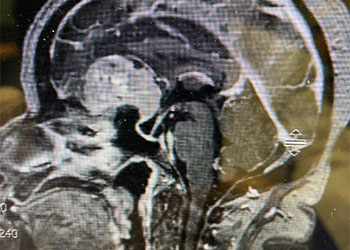

Brain:

Neurosurgeons Collaborate to Treat Giant Symptomatic Meningioma

Author: Ramin Rak M.D., F.A.A.N.S., F.C.N.S., Jonathan L. Brisman M.D., F.A.C.S., Read More!